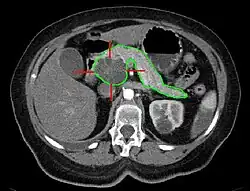

Rak w głowie trzustki, na zielono zaznaczono obrys trzustki, czerwone linie wskazują na lokalizację guza, obraz TK

Zamknięcie żyły głównej dolnej z powodu ucisku przez guz trzustki, obraz TK

Tomografia komputerowa jamy brzusznej poszerzona o skany klatki piersiowej i miednicy jest podstawową metodą pozwalającą na rozpoznanie i ocenę zaawansowania raka trzustki[197].

Czułość wielorzędowej tomografii komputerowej w wykrywaniu raka trzustki jest wysoka i wynosi 89–97%[200][201], choć czułość w wykrywaniu małych zmian poniżej 1,5 cm jest niższa i wynosi 67%[201][202]. Wykazano, że 70–80% chorych zakwalifikowanych na podstawie oceny zaawansowania w tomografii komputerowej jako chorzy z chorobą operacyjną nie zostało zdyskwalifikowanych po wykonaniu laparotomii z powodu większego zaawansowania choroby niż w ocenie za pomocą badań obrazowych i wykonano u nich zabieg chirurgiczny[203][204][197].

Typowo w tomografii komputerowej rak trzustki jest widoczny jako słabo odgraniczona, hipodensyjna masa w stosunku do niewzmocnionego w TK miąższu trzustki[201]. W 11–27% przypadków guz jest izodensyjny w stosunku do miąższu trzustki i jest niewidoczny lub mało widoczny w tomografii komputerowej[201]. Podejrzenie raka trzustki budzi również powiększenie części lub całego narządu, odcinkowe, dystalne poszerzenie przewodu trzustkowego, zatarcie budowy zrazikowej i widoczna martwica w trzustce[96].

W diagnostyce raka trzustki zaleca się stosowanie tzw. protokołu trzustkowego, który polega na wykonaniu wielu cienkich poprzecznych skanów cieńszych niż 3 mm oraz odwzorowania czołowego i strzałkowego. Następnie podaje się kontrast i ocenia się fazę miąższową trzustki (późna faza tętnicza) po 35–50 s po podaniu kontrastu oraz ocenia fazę wrotną po 60–90 s[201]. Jednocześnie z kontrastem doustnie podaje się dużą ilość wody celem wypełnienia żołądka i dwunastnicy[205]. Faza miąższowa trzustki ma na celu maksymalne wzmocnienie prawidłowego miąższu trzustki i zwiększenie widoczności hipodensyjnego raka trzustki. W tej fazie ocenia się również stosunek guza do ważnych naczyń krwionośnych, w tym pnia trzewnego i tętnicy krezkowej górnej[201][206][207]. Faza wrotna pozwala na ocenę obecności przerzutów w wątrobie oraz ocenę nacieku ważnych naczyń żylnych, w tym żyły wrotnej, żyły głównej dolnej, żyły krezkowej górnej i żyły śledzionowej. Rekonstrukcje czołowe i strzałkowe są przydatne w ocenie lokalnego zaawansowania guza oraz zajęcia ważnych naczyń krwionośnych[201].